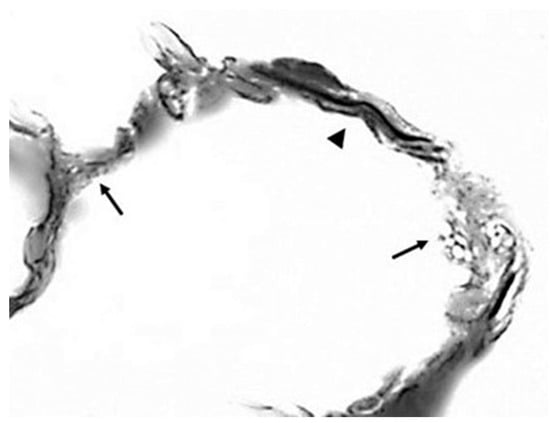

Although this model greatly simplifies the actual role of differential mechanical forces on lung elastic fibers of variable thickness and orientation, it nevertheless provides a useful visual and conceptual representation of the overall effect of these forces on the elastic fiber network, particularly with regard to elastin crosslinks. The unraveling and fragmentation of the damaged elastic fibers would increase their susceptibility to enzymatic breakdown, causing the further release of free DID (Figure 5). This process may be exacerbated by the uneven distribution of mechanical forces, which could increase the strain on DID, resulting in the separation of their lysyl side chains from the surrounding amino acids.

Figure 5.

Photomicrograph showing the fragmentation (arrows) and unraveling of elastic fibers (arrowhead). Reprinted with permission from [].